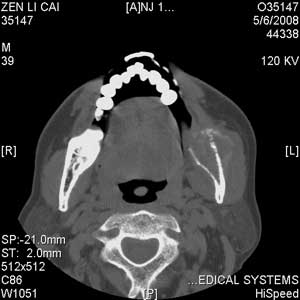

以下是引用jiangjing在2008-5-28 15:56:00的发言:[br]下颌骨左侧部骨质破坏,轻度膨胀,瘤骨形成,软组织肿胀考虑 恶性骨肿瘤-----肉瘤类